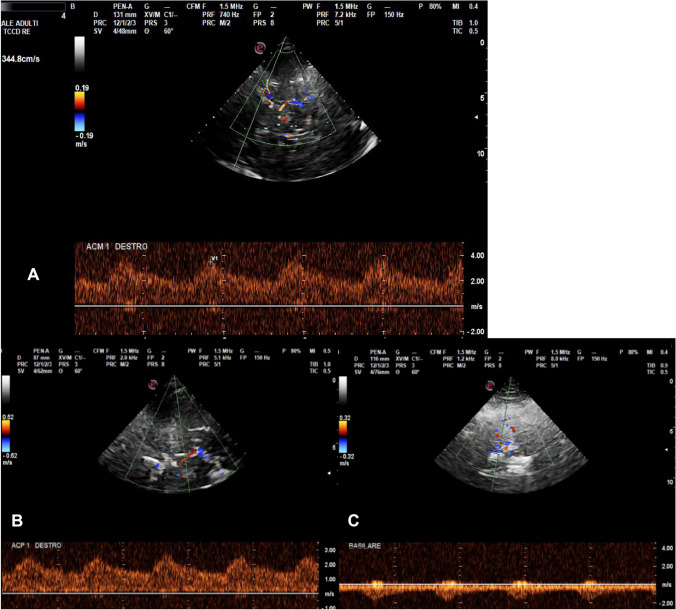

Laboratory investigations for autoimmune disease were all normal. Subsequently performed brain MRI and MR angiogram (MRA) documented diffuse and multifocal narrowing and irregularities of intracranial vessels (Fig. 2). A thin cortical convexity SAH and two restricted-diffusion areas indicating small recent ischemic lesions were also detected with MRI.

Fig. 2.

Cerebral angiography (A) and magnetic resonance angiography (MRA) (B) depicting remarkable smooth multifocal widespread narrowing and irregularities in the vessels of both anterior and posterior intracranial circulation

Finally, digital subtraction angiography (DSA) was compatible with multifocal vasoconstriction of middle, anterior, pericallosal, and posterior cerebral arteries of both sides (Fig. 2), while vascular malformations or saccular aneurysms were ruled out. Based on clinical history and instrumental findings, a diagnosis of reversible cerebral vasoconstriction syndrome (RCVS) was made.